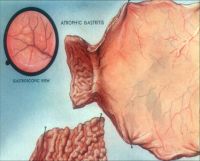

2.慢性萎缩性胃炎根据发病是否与自身免疫有关及是否伴有恶性贫血,分为A、B型;A型属于自身免疫性疾病,患者抗壁细胞抗体(PCA)及抗内因子抗体(IFA)阳性,并伴有恶性贫血,病变主要位于胃体和胃底部;B型多见于胃窦部,无恶性贫血;两者胃粘膜改变相似;胃镜见胃粘膜:由正常的橘红色变为灰色或灰绿色,粘膜层变薄、皱襞变浅甚至消失、粘膜下血管透见,表面有细颗粒、偶见出血糜烂;显微镜可见淋巴细胞、浆细胞浸润、肠上皮化生、腺上皮化生、不典型增生;

慢性胃炎病人病程迁延,大多无症状或症状很轻,部分病人表现为消化不良的症状:如上腹部不适,无规律性腹痛、反酸、嗳气、恶心呕吐等,少数病例出现较重的症状:疼痛、厌食、消瘦,酷似胃癌的表现,自身免疫性胃炎可有明显厌食、消瘦,伴有贫血、舌炎等。慢性胃炎的命名很不统一。依据不同的诊断方法而有慢性浅表性胃炎、慢性糜烂性胃炎、慢性萎缩性胃炎、慢性胆汁返流性胃炎、慢性疣性胃炎、药物性胃炎、乙醇性胃炎等等。